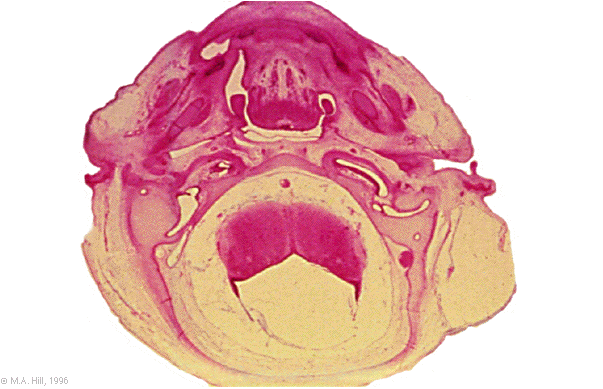

Hum B6